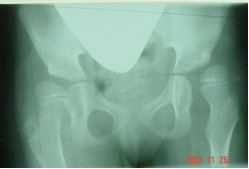

Załączony radiogram przedstawia stawy biodrowe 5-letniego dziecka z mózgowym porażeniem dziecięcym zaklasyfikowanym jako GMFCS V. Oceniana w oparciu o przedstawione radiogramy niestabilność stawu biodrowego lewego stanowi wskazanie do:

Pytanie 45